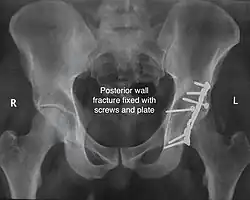

Posterior wall fracture fixed with screws and plate -